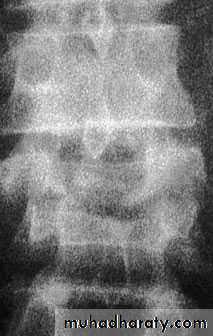

Imaging

X-rays The anteroposterior x-ray may show loss of

height or splaying of the vertebral body with a crush

fracture

Severe axial compression may ‘explode’ the vertebral body, causing failure of both the anterior and the middle columns. The posterior column is usually, but notalways, undamagedAnteroposterior x-rays may show

spreading of the vertebral body with an increase of the interpedicular distance